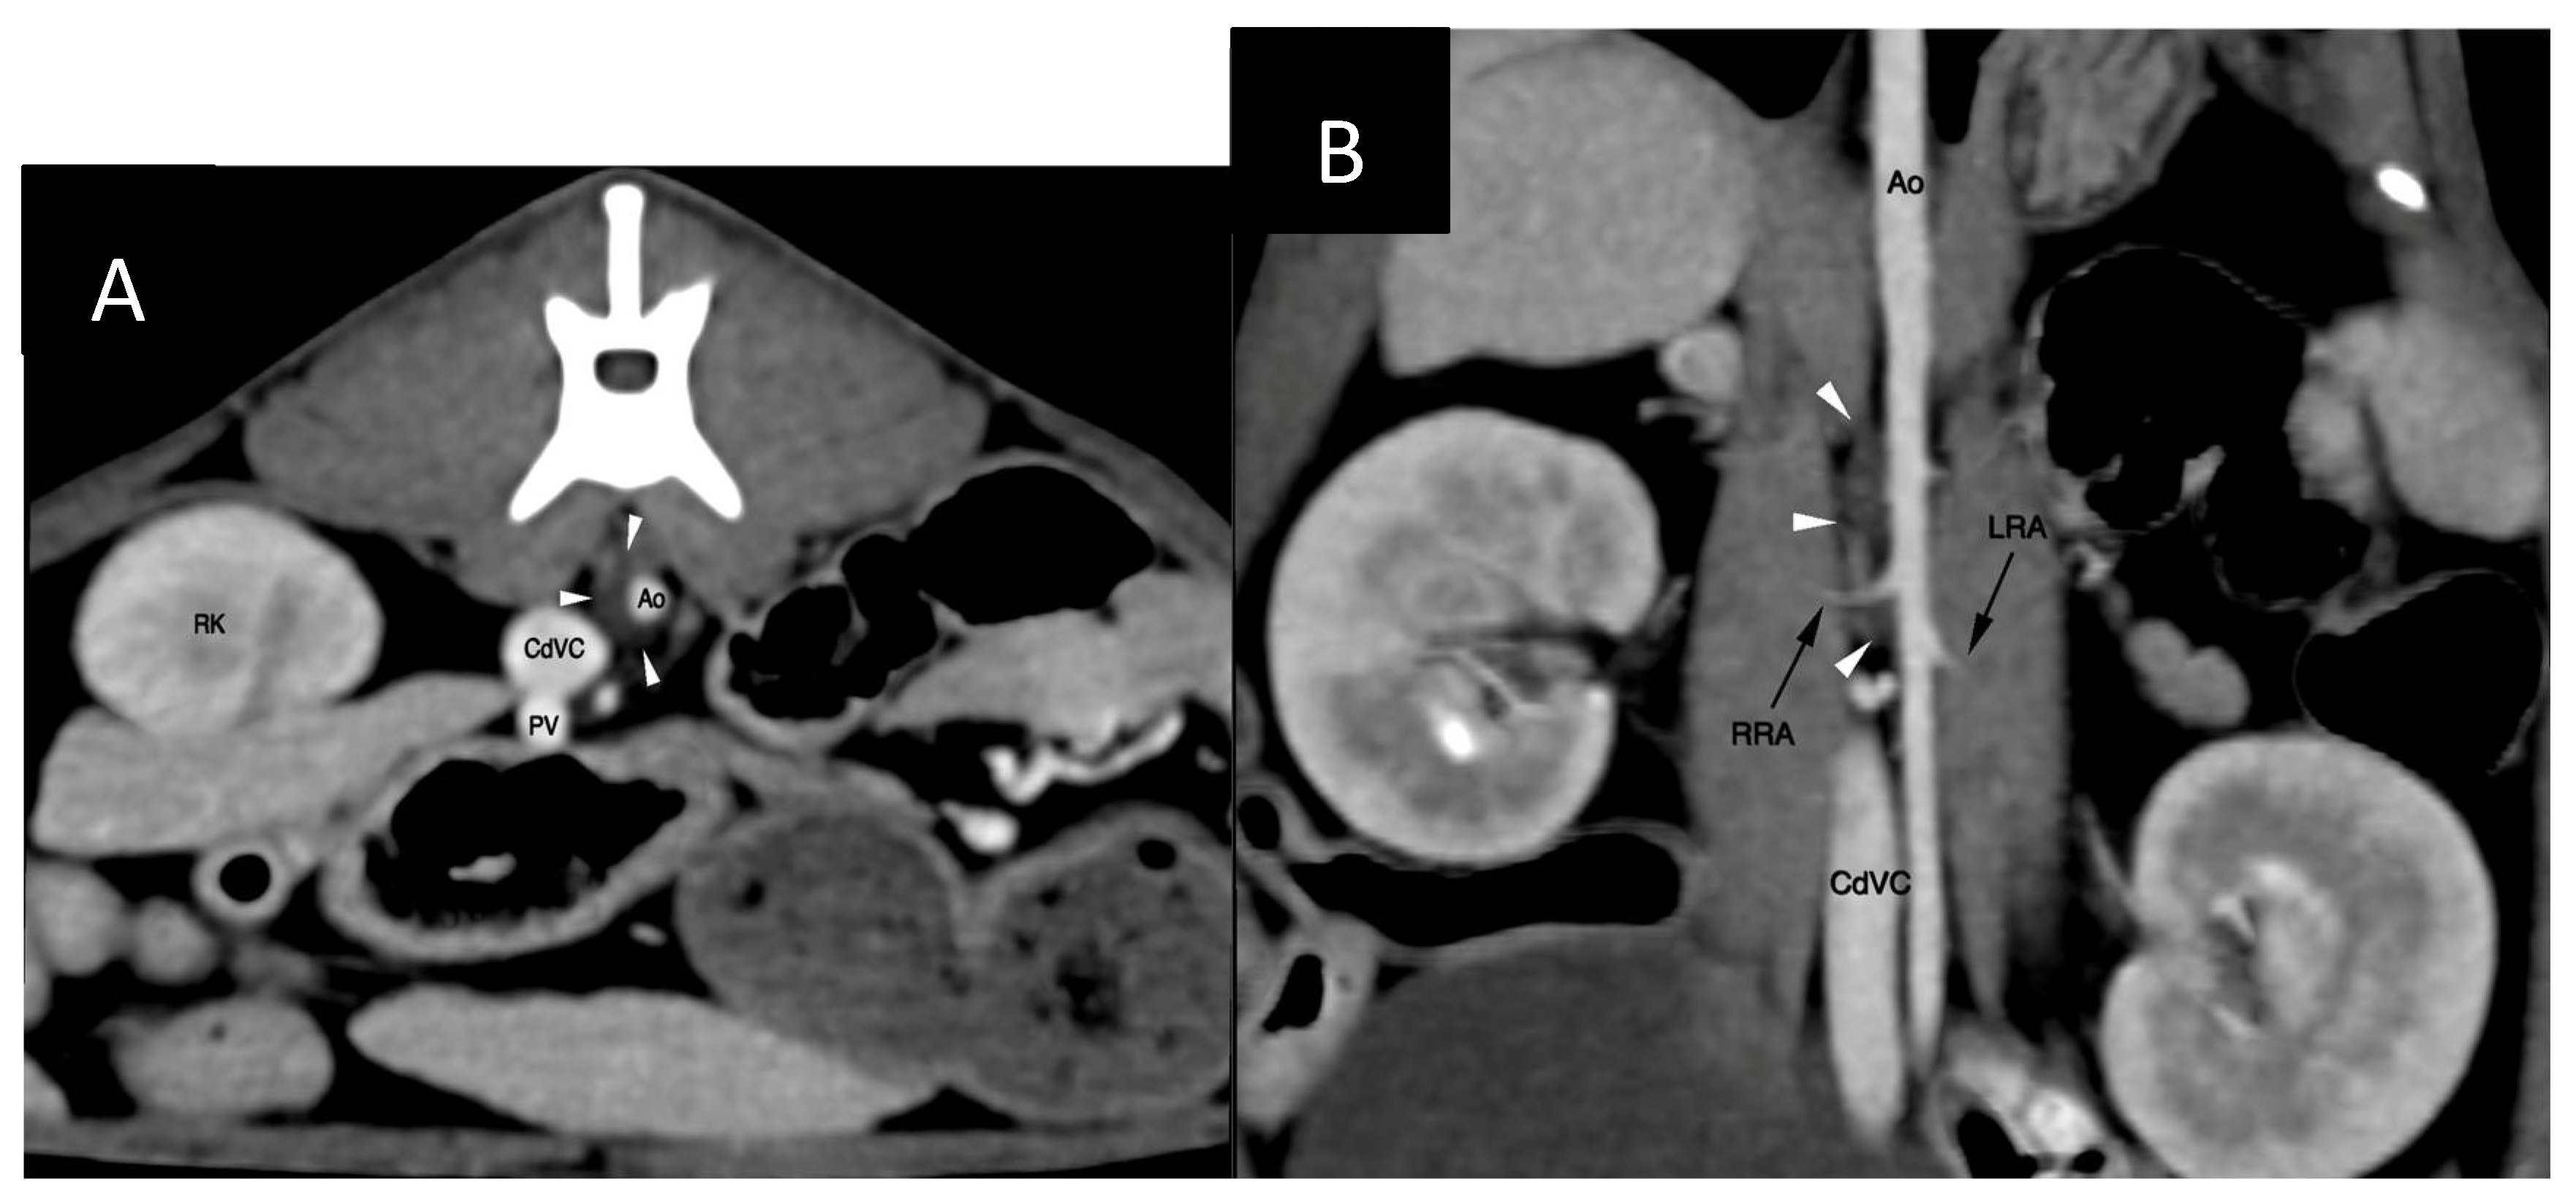

The cisterna chyli (CC) was visible at the level of the L2-L3 lumbar vertebrae, being crescent-shape and located slightly to the right of the aorta (Figure 2). The proximal part of the thoracic duct was visible but quickly became indistinct cranially. No contrast opacification of the lymphatic system could be appreciated on post-intravenous contrast CT. Delayed post-intravenous contrast series as reported by Guarnera [13] were not acquired, neither was computed tomography lymphangiogram (CTLA) performed.

To overcome the technical challenges mentioned by Singh et al. [20] the author decided to apply certain modifications. Ultrasound guidance was used to puncture the cisterna chyli and patient positioning and needle trajectory were inferred from the computed tomography study. The dorsoventral dimension of the CC was advantageous in this patient (Figure 2) and allowed for a relatively uncomplicated access, although great care needed to be maintained to prevent iatrogenic injury/laceration to the aorta and the right renal artery and vein (Figure 4). Ultrasound guidance provided real-time monitoring of the trajectory of the needle and continued fanning of the ultrasound probe allowed avoidance of the neighbouring vascular structures. No vascular sheath was used in this case to minimize number of exchanges and reduce the risk for loss of access. Instead, the microcatheter was inserted through the needle, a concept that is utilized during placement of epidural catheters.

Figure 2. Pre-TDE computed tomography images: transverse (A) and dorsal plane (B) multiplanar reformations (MPRs). Left is to the right on both images; dorsal is to the top on panel A; cranial is to the top on panel B. The cisterna chyli is delineated with white arrowheads. Ao – aorta; CdVC – caudal vena cava; PV - portal vein; RK – right kidney; RRA – right renal artery; LRA –left renal artery.